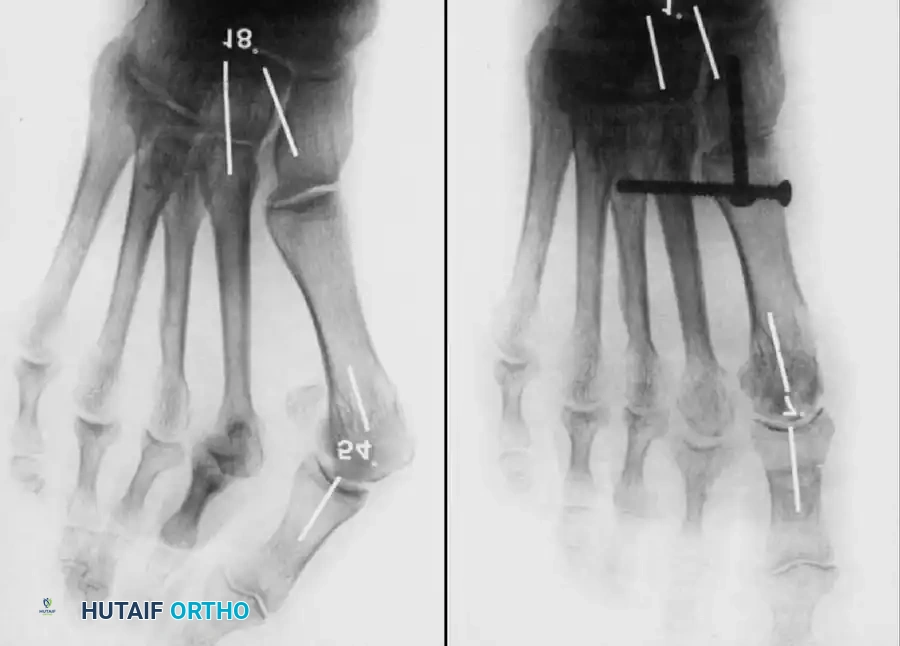

Keller Resection Arthroplasty The Keller procedure combines resection hemiarthroplasty of the fi rst metatarsophalangeal joint with removal of the medial eminence of the fi rst metatarsal (Fig. 78-28). Although removing the base of the proximal phalanx decompresses the joint and mobilizes the hallux, allowing marked correction of valgus, the varus of the fi rst metatarsal is not corrected, and maintaining correction of the valgus of the hallux is diffi cult. Other complications of the Keller procedure have been emphasized in the literature to such an extent (with neither the incidence nor the severity of such complications clearly documented) that the indications for this procedure have been limited severely. In our experience, however, complications are uncommon if patients are selected carefully. Modifi cations in the original technique also have allowed expansion of the indications for the Keller bunionectomy. Candidates for the Keller procedure are patients older than 50 years with moderate-to-severe hallux valgus (30 to 45 degrees); intermetatarsal angles of 13 degrees or less, indicating mild-to-moderate metatarsus primus varus; and pain over the medial eminence with any shoe worn, so the variety of shoes the patient can wear is severely limited. An incongruous fi rst metatarsophalangeal joint caused by

Fig. 78-26 Modifi ed McBride bunionectomy (DuVries; Mann). A, Medial capsule of second metatarsophalangeal joint is sutured to lateral capsule of fi rst metatarsophalangeal joint with interposition of released adductor hallucis. B, Medial capsular resection. C, Confi guration after capsular resection. D, After capsular imbrication, hallux should rest in neutral position or not exceed 5 degrees of varus. E, Postoperative dressing technique (Mann). ( E after Beverly Kessler; courtesy of LTI Medica and The Upjohn Company.) lateral subluxation of the phalanx on the metatarsal head, severe lateral displacement of the sesamoids, and any evidence of degenerative cartilage changes in the joint all are radiographic indications for the Keller procedure. Two modifi cations in technique can expand these indications, however, to include patients with more severe deformities (Fig. 78-29) (but not to include younger patients): fi bular sesamoidectomy and lateral displacement of the fi rst metatarsal. Using these modifi cations, Donley et al. obtained an average 18-degree correction of the metatarsophalangeal angle and an average 6-degree correction of the intermetatarsal angle in 38 patients (50 feet);

95% of patients were satisfi ed with their results. Patients with 50 degrees or more of valgus of the hallux (18 to 20 degrees of varus of the fi rst metatarsal), complete lateral dislocation of the sesamoids, marked degenerative changes, and severe pronation of the hallux may benefi t functionally and cosmetically from alterations of the standard technique.

Fig. 78-29 Severe hallux valgus with bursa formation in 70-year-old woman. A and B, Anteroposterior and lateral clinical photographs of patient’s right foot. C, Correction of deformity by modifi ed Keller procedure. D, Preoperative and postoperative weight bearing radiographs of same patient.

The following modifi cations of the Keller technique can expand the indications for use with more severe deformities.

• When the sesamoid has been removed, insert two 0.062-inch Kirschner wires retrograde from the tip of the toe 2 to 3 mm plantar to the nail bed, leaving about 5 to 7 mm of the pins exposed at the base of the phalangeal remnant to help align the phalanx on the metatarsal before antegrade passage of the pins into the metatarsal (Fig. 78-31F).

LATERAL DISPLACEMENT OF THE FIRST METATARSAL

• Push the metatarsal laterally several times. Occasionally, this does not move the metatarsal, but some lateral mobility usually is present.

AFTERTREATMENT A fi rm-soled, postoperative shoe is worn, and weight bearing is allowed to tolerance with or without the assistance of crutches or a walker. Bathroom privileges only are allowed for the fi rst 72 hours. The foot is elevated except during meals and bathroom visits. After this period, the patient may be up and about as symptoms allow. Taking more pain medication to allow increased activity is discouraged. For 7 to 10 days after surgery, the foot should be elevated when the patient is sitting. The dressing is changed at 19 to 23 days, and the wires remain in place for 21 to 28 days. If the hallux migrates proximally on the wires and the wires protrude too far before time to remove them, the tips are cut 1 to 2 mm distal to the skin edge. The Kirschner wires are removed in the offi ce by placing a large or medium-sized needle holder longitudinally over the tip of the wire, rotating it back and forth gently and pulling with gentle traction. To prevent excessive bleeding, the foot is elevated for 5 minutes after the wires have been removed. A good method of elevation is to place the patient supine with the unoperated knee fl exed 90 degrees and the foot fl at on the table, and then to place the ankle of the operated foot on the fl exed knee. A small plastic strip bandage is placed over the holes when the bleeding has stopped. A small or medium-sized toe spacer (commercially available) is worn in the fi rst web for an additional 4 to 6 weeks; this spacer is removed only for bathing. A wide, soft shoe is allowed after the pins have been removed. Dress shoes are allowed only after most of the edema has resolved, which may take 3 to 4 months. The expected results are a satisfactorily well-aligned hallux with 40 to 50 degrees of motion at the metatarsophalangeal joint, relief of pain, and some improvement in the variety of shoes that can be worn.